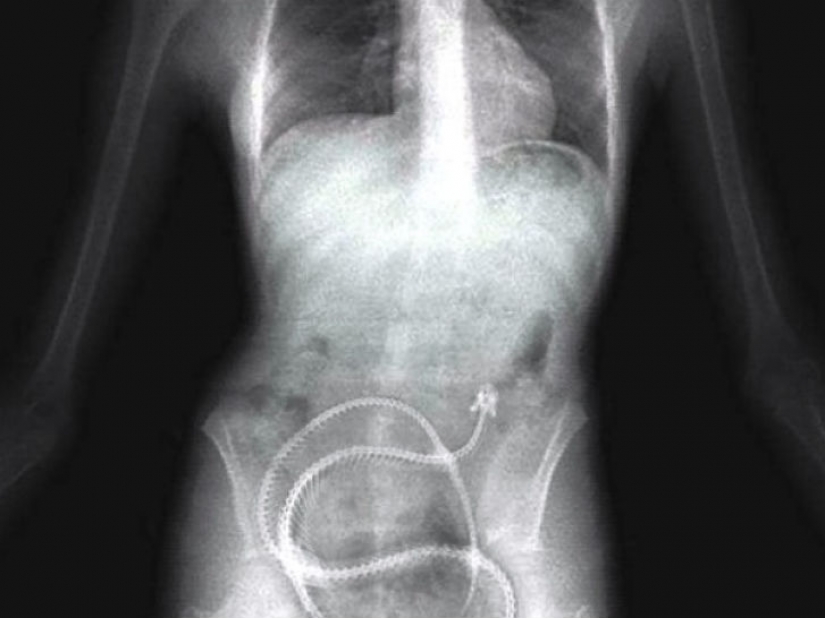

Y los presos de la ingestión de un teléfono celular.